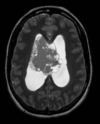

40 anos, Convulsão SWI

Oligodendroglioma Envolve córtex e substância branca Calcificação em 70 - 90% dos casos. Realce discreto ou ausente.